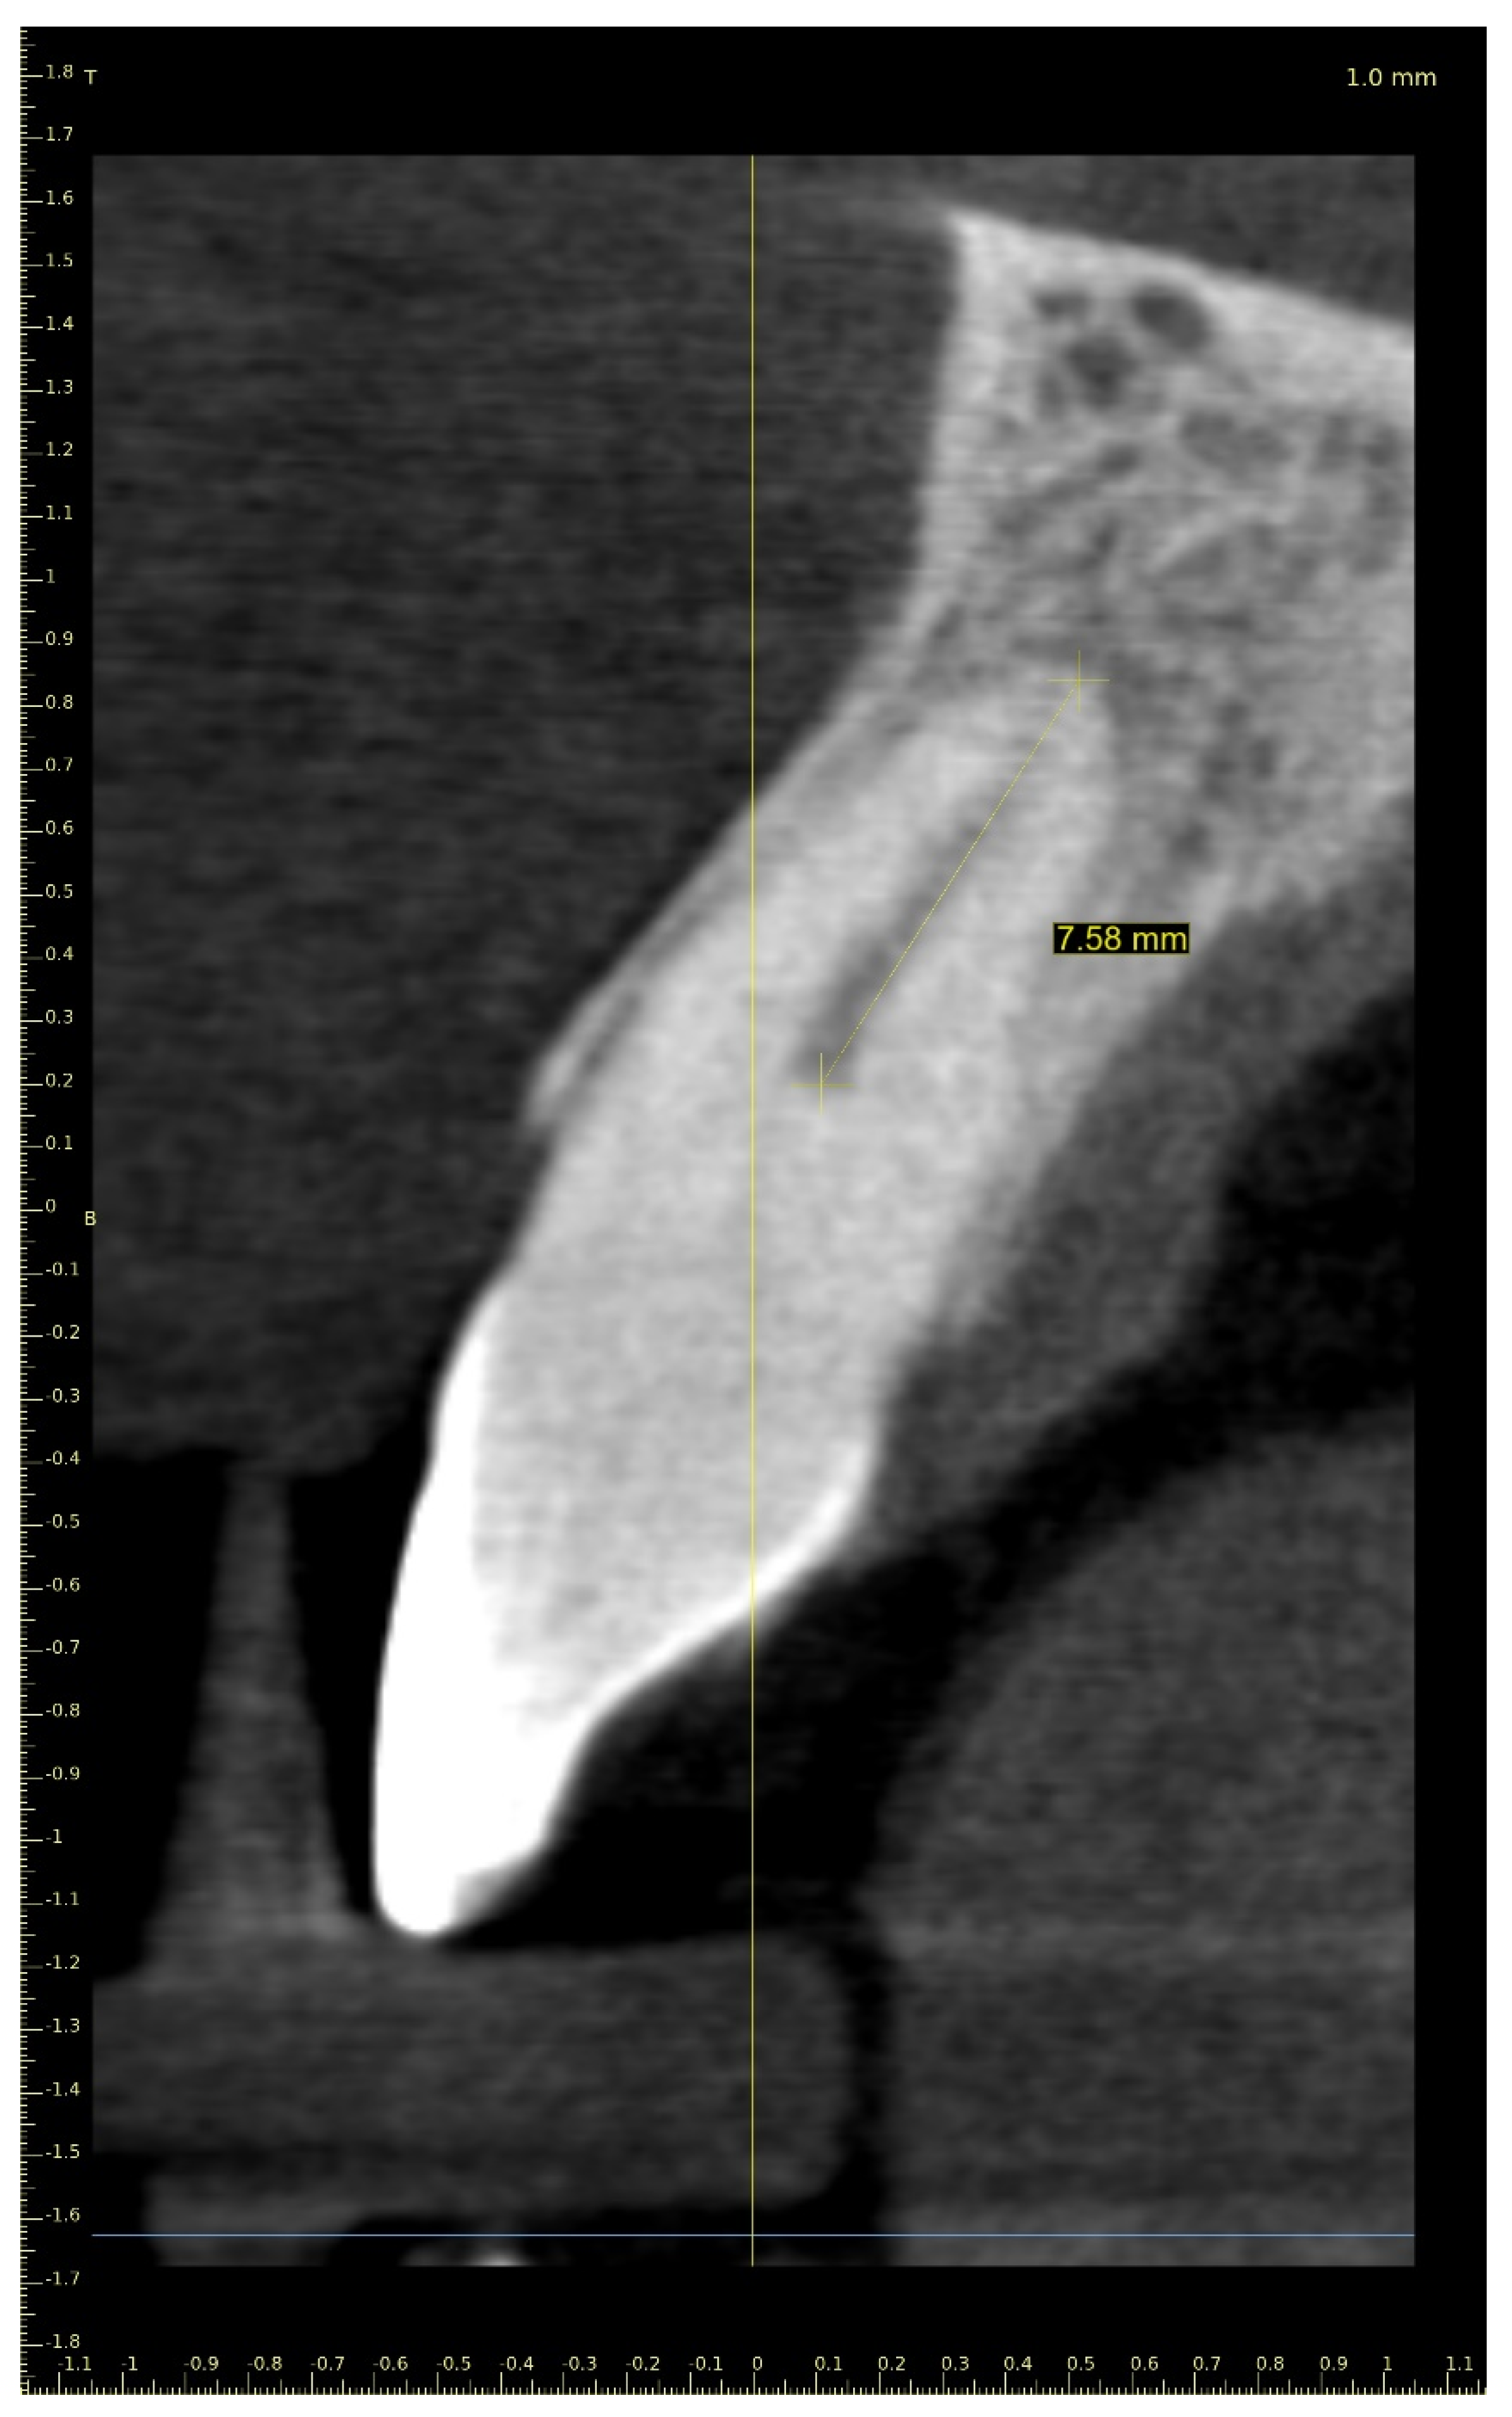

Three-Dimensional Treatment Plan

Three-Dimensional Treatment Plan and RCT